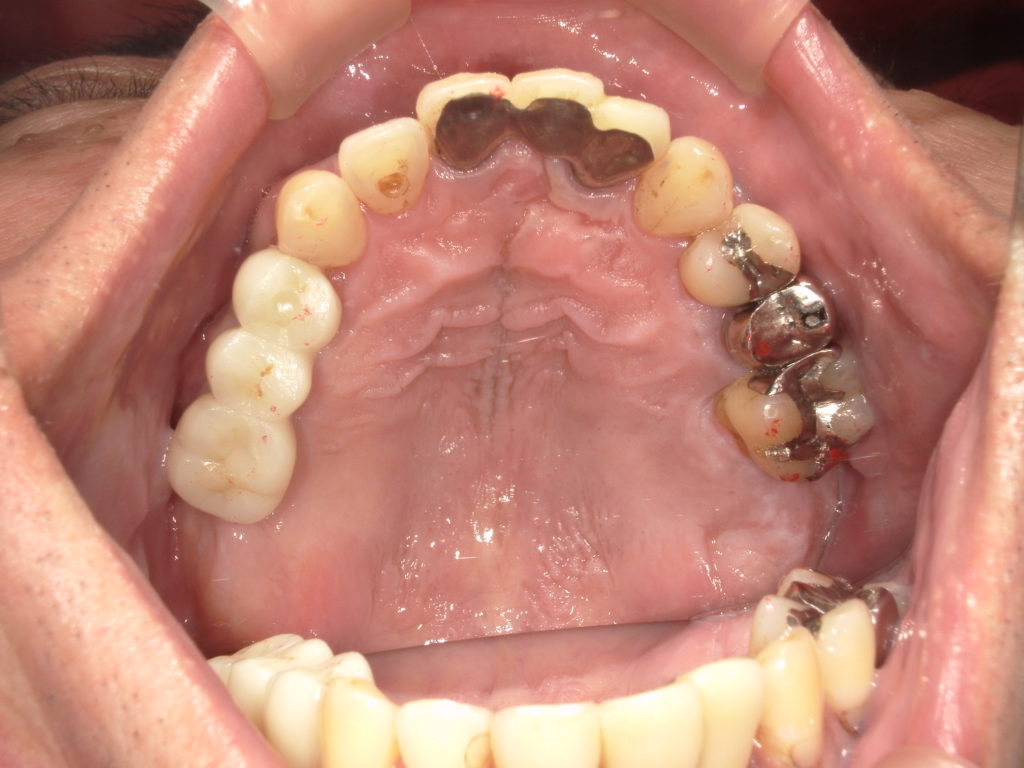

Y様インプラント実例 #44

左の上下の奥歯をインプラントで治療しています。

左下の奥歯は歯を抜くのと同時にインプラントの埋め込みを行っています。

被せものは上下、セラミックスで作っています。

治療前

治療後